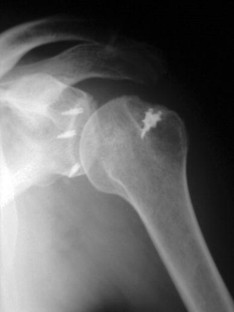

Fig. 4